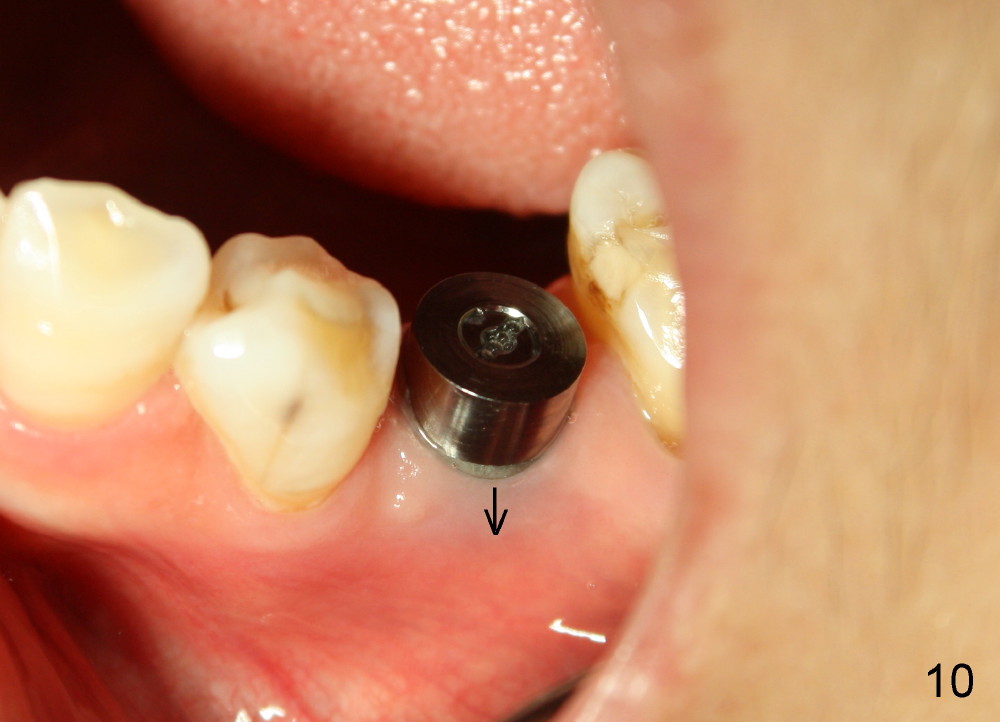

Six months postop, bone density around the implant increases (Fig.9).  There is slight gingival recession buccal to the implant (Fig.10 arrow).  A short abutment is placed and prepared short (Fig.11 A); the margin is prepared as low as possible in the implant (I).